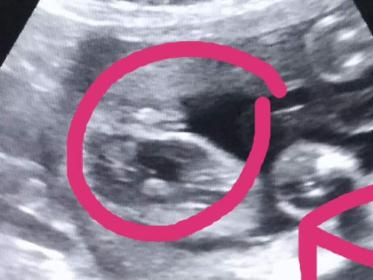

Can anyone tell me if this is a definite girl? i totally see a "hamburger Im sure it is (though Im no expert) my husband is denial and says it could be boy. My doc has confirmed but I guess my hubby has heard the stories of being told girl and then turning out its a boy....... This was taken @23 weeks. We have four boys and an eldest girl. I have been dying for another little princess in the home lol.